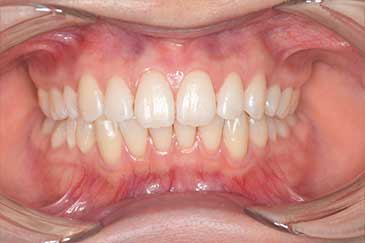

Before

After

基本情報

| 主訴 | 見た目をきれいにしたい |

| 治療期間 | 6ヶ月 |

| 治療費 | ジルコニアボンド(セラミックの被せもの)¥165,000×7(税込み) オフィスホワイトニング4回 ¥4,400×4(税込み) ホームホワイトニング¥11,000 |

| リスク・副作用 | かみ合わせがとても強い方の場合、稀に割れてしまうことがあります。 |

| 先生からの提案 | 上の前歯6本と右下の2番目の歯はセラミックの被せもので治療。 残りの下の前歯5本はプラスチックの材料で虫歯を治療し、 ホワイトニングをおこないました。白くなったご自身の歯の色に合わせてセラミックの 被せものを作成しています。 模型上で完成後をシュミレーションし、上の歯茎の位置をきれいに見えるように 揃えています。(外科処置はしていません) |